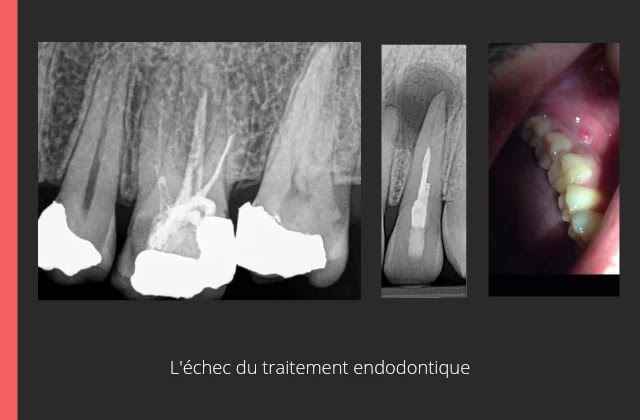

II. Les signes d'échec d'un traitement endodontique:

Les signes d'échec d'un traitement endodontique apparaissent cliniquement ou radiologiquement; on peut citer: la persistance des symptômes, la présence d'une fistule ou une tuméfaction, une douleur au test de percussion, une sinusite d'origine dentaire, ou une adénopathie cervico-faciale.

À la radiographie on remarque des espaces non obturé ou un dépassement excessif des matériaux d'obturation, un élargissement desmodontal supérieur à 2mm, l'absence de guérison et de réparation osseuse d'une lésion, ou l'apparition d'une nouvelle lésion radio-claire ou radio-opaque.